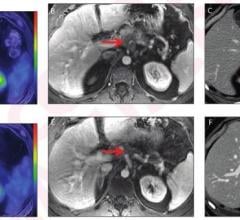

PET-MRI combines positron emission tomography (PET) and magnetic resonance imaging (MRI) into one imaging system. Positron emission tomography–magnetic resonance imaging (PET-MRI) is a hybrid imaging technology that incorporates magnetic resonance imaging soft tissue morphological imaging and positron emission tomography functional imaging.

July 31, 2024 — In a head-to-head comparison with FDG PET/CT, FDG PET/MRI demonstrated comparable or superior diagnostic ...